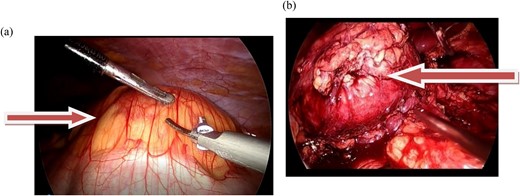

Contrast-enhanced CT revealed an 8 × 5.4 × 5.4 cm, well-defined, intensely enhancing retroperitoneal mass anterior to the left kidney, with an arterial supply from the left second and third lumbar arteries. Marked soft tissue stranding suggested a neurogenic tumor, likely an extra-adrenal pheochromocytoma or paraganglioma (Fig. 1a and b). A core biopsy from another center also suggested paraganglioma.

(a and b) axial and coronal computed tomographic scans, respectively, show intensely enhancing round to oval soft tissue density mass in the left retroperitoneal area anterior to the left kidney.